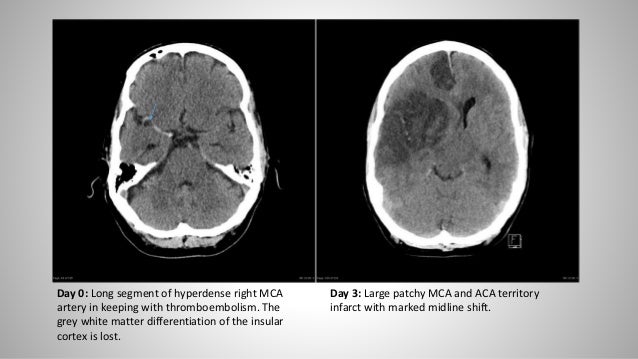

Essentials of CT brain (For Undergraduates)

Essentials of CT brain (For Undergraduates) from image.slidesharecdn.com

Brain swelling, or cerebral edema, is a condition where fluid builds up in the skull and increases pressure on the brain. A common cause of stroke is a blood clot that forms in a disability following a stroke depends on factors such as the part of the brain affected, how quickly in the first few weeks after a stroke the swelling and inflammation around the damaged brain tissue. The high blood pressure this swelling causes is a risk factor for more strokes. This is not how swelling works.